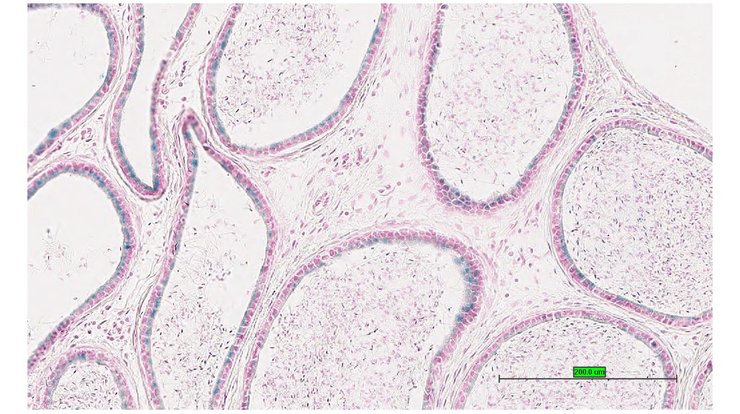

TS28: prostate gland Present UC Davis_1876904

Specimen UC Davis_1876905: postnatal adult; Fosbtm1b(KOMP)Wtsi/Fosb+ (more )

Structure Level Pattern Image Note

TS28: prostate gland Present UC Davis_1876905